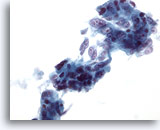

画像 76

膵FNA、膵腺癌膵管癌を高倍率で観察したもの。合胞化を来す悪性細胞による疎性の集塊のほか、孤立性に散在するものも認められます。形状は立方形のものもあれば円柱状のものもみられ、N/C比は高値を示します。

60倍

画像 76

膵FNA、膵腺癌

膵管癌を高倍率で観察したもの。合胞化を来す悪性細胞による疎性の集塊のほか、孤立性に散在するものも認められます。形状は立方形のものもあれば円柱状のものもみられ、N/C比は高値を示します。

60倍